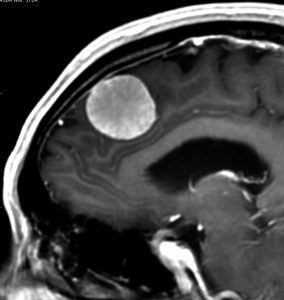

典型的な髄膜腫

この髄膜腫は中程度の大きさのものです。円蓋部髄膜種という最も多い最も手術の簡単なタイプです。麻痺や失語症やてんかんなどの症状はありません。とても美しくて若い女性の髄膜腫でしたが,子供に遺伝はしませんし,癌などと違ってタバコなどこれといった原因がなくて発生するものです。

MRIでの髄膜腫の見え方は撮影の仕方によっていろいろです。左からT1強調画像,T2強調画像,フレア画像といいます。腫瘍の横に小さく白い領域がありますが,これは脳の腫れた部分で脳浮腫といいます。髄膜腫があると周囲に脳浮腫が生じることがあります。

最も見やすいのが,ガドリニウム造影剤を注射して撮影するものです。一般的に髄膜腫は造影剤で白く映し出されます。この腫瘍は左脳側にあります。MRIの軸面という輪切りの写真では左右が逆になりますから注意してください。脳を下から見た図になっています。MRIはいろいろな方向から腫瘍を見ることができますが,右は冠状断という正面から見た図です。よく見ると腫瘍の上と下のはじっこに線状に糸を引いたように造影される部分があります。これをテールサイン(しっぽのサイン)といいます。腫瘍が硬膜に沿って延びている可能性があることを示しています。

手術後のMRIです。腫瘍は全部取れていて後遺症もありません。圧迫されて変形していた脳はきれいに元に戻っていますし脳浮腫も消えました。一般的に若い人の脳ほどきれいに元に戻ります。注意しなければならないのは,少しでも取り残した場合には,何年か後に10%-20%くらいで再発があることです。もちろん完全に取れた時の再発はほとんどありません。